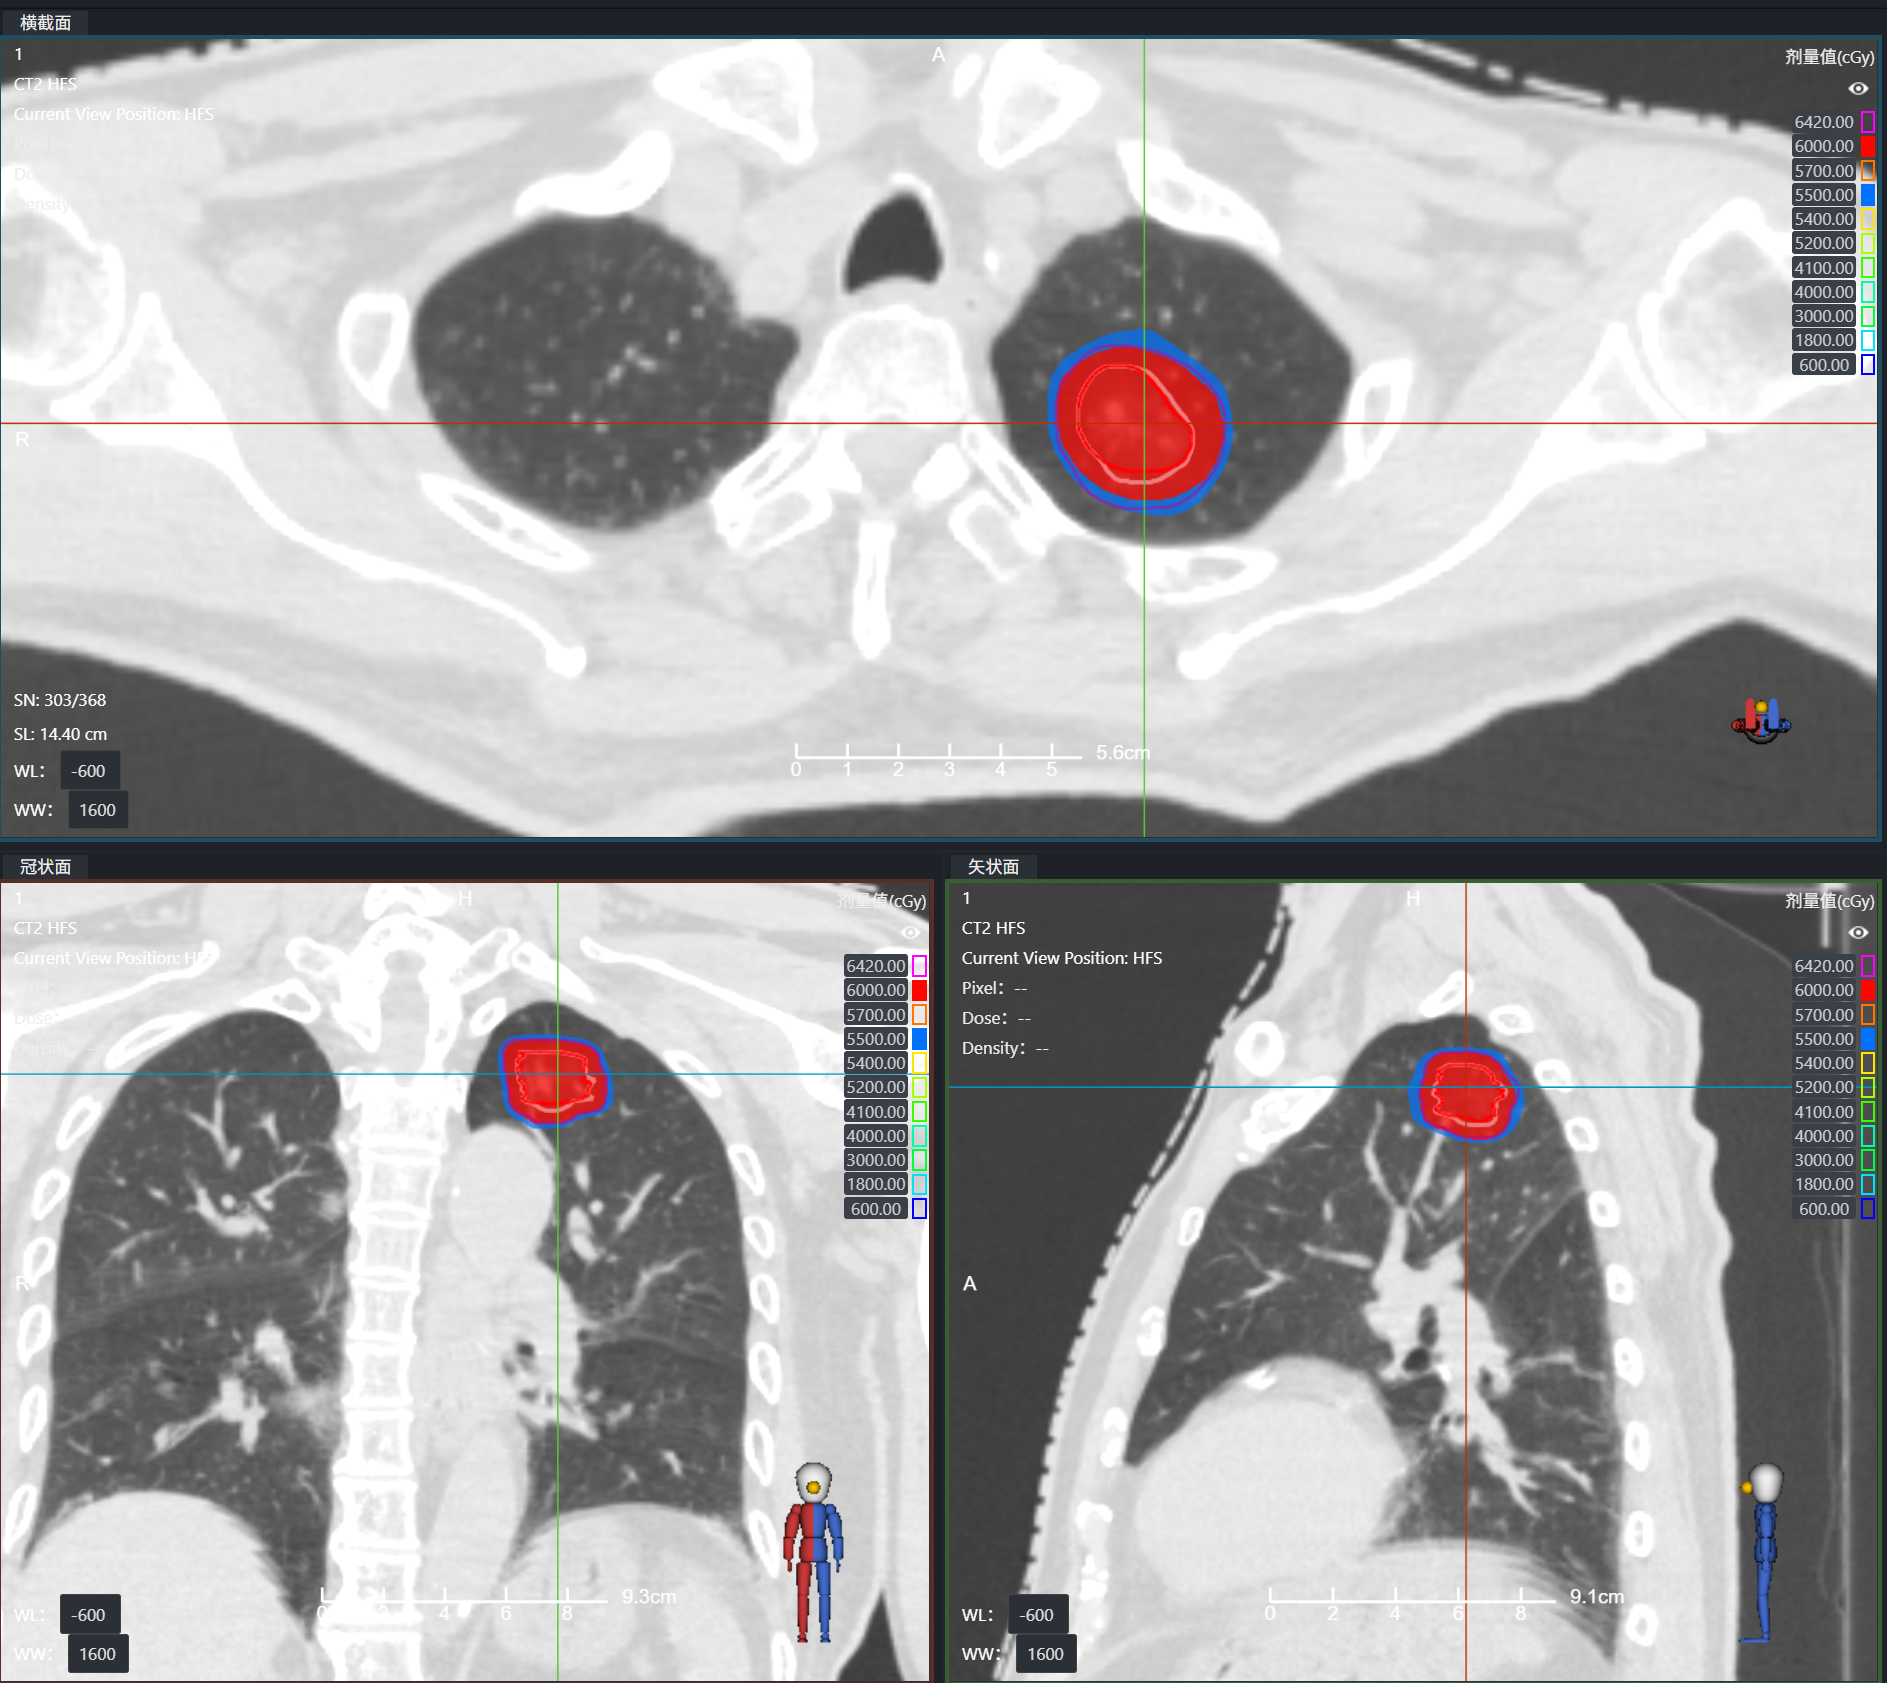

年龄与身体状况,绝非抗击癌症的阻碍!在我院,多学科协作正为高龄、无法耐受手术的肺癌患者点燃新希望。近期,两位80多岁的肺癌患者(爷爷/奶奶),通过SBRT(立体定向体部放疗)联合 4DCT(四维CT)的无创治疗,首次复查传来喜讯 —— 肺部病灶控制良好!

60岁的李女士(化名)直肠癌术后2年,复查时发现右肺新发病灶。得知这个消息她一度陷入绝望。手术做了,化疗也坚持完成了,癌症还是卷土重来了……抱着一丝希望,李女士来到和祐医院就诊。经过和祐医院肿瘤医学中心多学科团队(MDT)的深度会诊,放疗科、肿瘤内科、外科、影像科专家共同研判后,给出了一个关键结论:这并非广泛扩散的"全面战争",而是转移灶数量极为有限的"寡转移"状态!